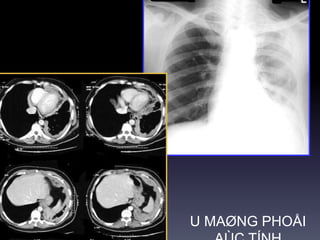

U maøng phoåi

*U xô maøng phoåi :

Thöôøng 80% laønh tính,20% xaâm laán

(chæ 1 oå).

-Khoái ñôn ñoäc ñaùy maøng phoåi, nhieàu

muùi,bôø roõ.

-Xaâm laán ngöïc daïng xaâm laán.

-Coù theå phaùt trieån vaøo raõnh maøng

phoåi.

*U maøng phoåi aùc tính

-Daøy maøng phoåi lan toaû.

-Traøn dòch maøng phoåi.

-Di caên phoåi.

U aùc tính maøng phoåi

PA,

decubitus

U xô laønh tính maøng

phoåi